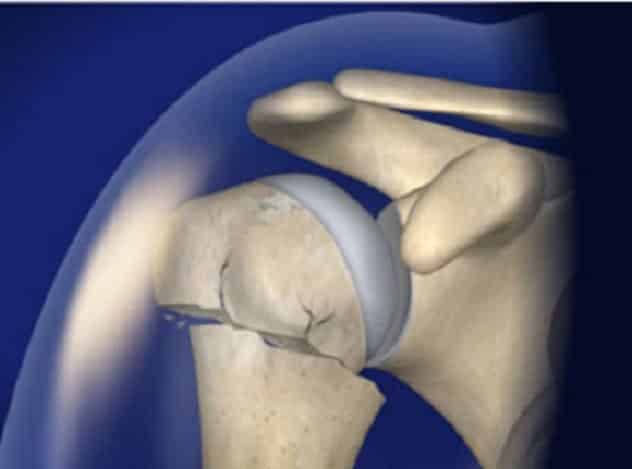

Эндопротезирование плечевого сустава

При наличии травмы, приведшей к раздроблению плечевой кости и возникновению асептического некроза головки, пациенту может быть рекомендовано эндопротезирование. В процессе операции применяются как однополюсные, так и тотальные эндопротезы. Врач выбирает подходящий тип протеза, основываясь на возрасте пациента и его общем состоянии здоровья.

Важно. Некоторые пациенты могут иметь противопоказания к эндопротезированию. В таких случаях им проводят артродез — операцию, целью которой является фиксация сустава в неподвижном состоянии.